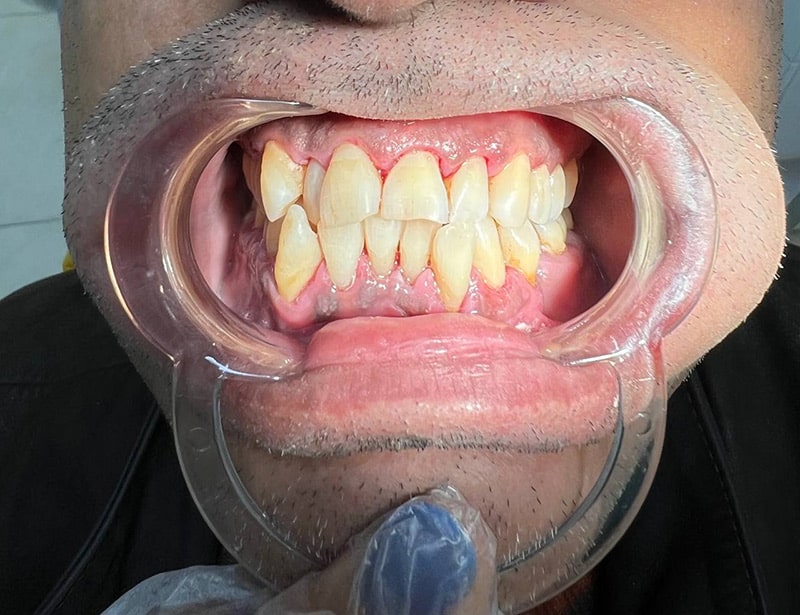

عکس های قبل و بعد جرم گیری و عصب کشی دندان پزشکی رایان

عکس های قبل و بعد جرم گیری و عصب کشی دندان پزشکی رایان

عکس های قبل و بعد نمونه های دندان پزشکی رایان